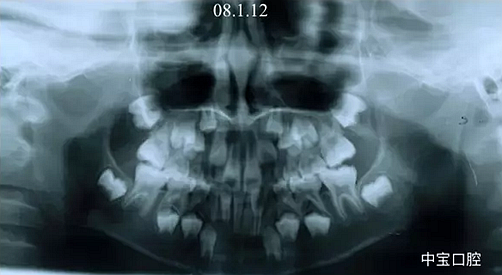

有一個七歲的小女孩,在替牙時媽媽發(fā)現(xiàn)孩子新長的牙不整齊,有一顆長到里面了,上下頜中線也不對稱,很著急就來到門診看牙。

經(jīng)過我臨床檢查和X線的診斷,決定早期干預,每三個月定期復診檢查一次,并拔掉了幾個乳牙和四個恒牙,正畸專業(yè)叫序列拔牙。

5.png

這個故事告訴我們,只有家長早點把孩子帶給正畸醫(yī)生檢查,才能早期發(fā)現(xiàn)早期治療。起到了事半功倍的效果。矯正以后還不容易復發(fā),因為從08年的初診到11年戴矯正器這三年多的時間里,孩子的牙齒是自己長好的。